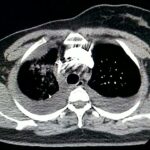

O diagnóstico de embolia pulmonar é feito com base na suspeita clínica e na realização de exames complementares. O principal exame para confirmar o diagnóstico é a angiotomografia de artérias pulmonares, um tipo especial de tomografia de tórax com contraste. Outros exames, como cintilografia pulmonar, ultrassom e angiografia, também podem ser utilizados.